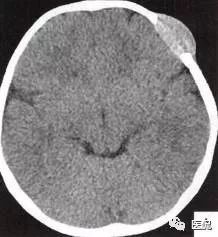

颅脑CT示:图A〜D,CT平扫示左侧额骨、蝶骨见溶骨性骨质缺损,边界清晰,周围无硬化边,伴有软组织肿块向脑外生长,边缘光滑,脑内无明显侵犯;

图E、F,横、 矢状位CT增强示软组织肿块轻度均匀强化,两病灶间亦见强化软组织影;